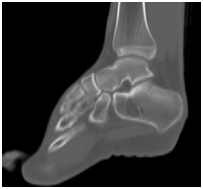

Twenty four year old male presented to us with left heel pain for nine weeks of duration. The onset of the pain was insidious and aggravated by weight bearing and prolonged standing. It was relieved with the use of analgesics and limb rest. There was no history of preceding trauma or rest pain. On examination there was no local swelling and skin changes. Deep tenderness was present over anteromedial aspect of calcaneum. Plain radiographs of the heel revealed well defined, lytic lesion in the calcaneum. Computed Tomographic scan of the same showed lytic lesion in the in the body of calcaneum just below the posterior facet. Provisional diagnosis of benign bone tumor was made and patient was planned for curettage and bone grafting.

Intraosseous lipomas are diagnosed with plain radiography and CT scan (Figure 1) (Figure 2A) (Figure 2B). Mainstay of treatment is conservative; however surgery is indicated in severe pain not responding to conservative treatment, impending pathological fracture and malignant transformation (Figure 3). Treatment for these tumors is curettage and bone grafting (Figure 4) with good prognosis.8–10

Figure 1 Plain radiograph lateral view showing lytic lesion in calcaneum.